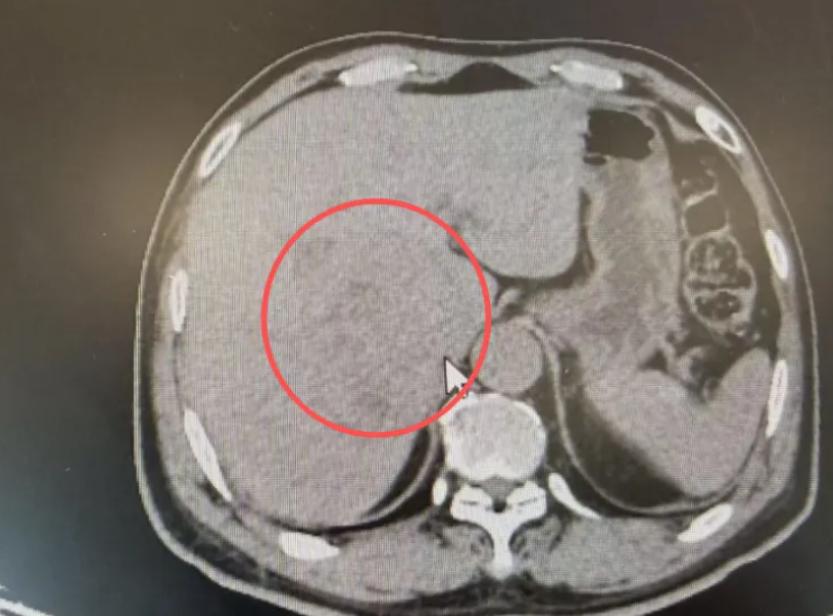

七旬患者王先生(化名)3个月前发现自己的尿液颜色异常发黄,严重时甚至黄得如浓茶水般。同时,他的上腹部也经常胀痛,并伴随反酸和烧心的感觉,这些症状似乎在暗示着某种严重疾病,让他非常焦虑。